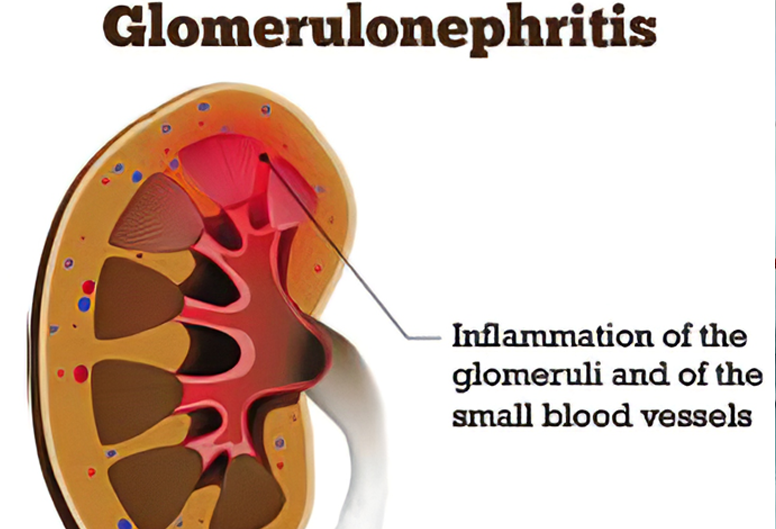

Fellowship in Glomerular Diseases (GlomCon) by the Glomerular Disease Study and Trial

Consortium.